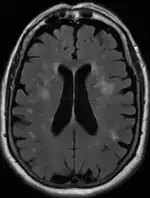

Leukoaraiosis is a particular abnormal change in appearance of white matter near the lateral ventricles. It is often seen in aged individuals, but sometimes in young adults.[1][2] On MRI, leukoaraiosis changes appear as white matter hyperintensities (WMHs) in T2 FLAIR images.[3][4] On CT scans, leukoaraiosis appears as hypodense periventricular white-matter lesions.[5]

The term "leukoaraiosis" was coined in 1986[6][7] by Hachinski, Potter, and Merskey as a descriptive term for rarefaction ("araiosis") of the white matter, showing up as decreased density on CT and increased signal intensity on T2/FLAIR sequences (white matter hyperintensities) performed as part of MRI brain scans.

These white matter changes are also commonly referred to as periventricular white matter disease, or white matter hyperintensities (WMH), due to their bright white appearance on T2 MRI scans. Many patients can have leukoaraiosis without any associated clinical abnormality. However, underlying vascular mechanisms are suspected to be the cause of the imaging findings. Hypertension, smoking, diabetes,[3] hyperhomocysteinemia, and heart diseases are all risk factors for leukoaraiosis.